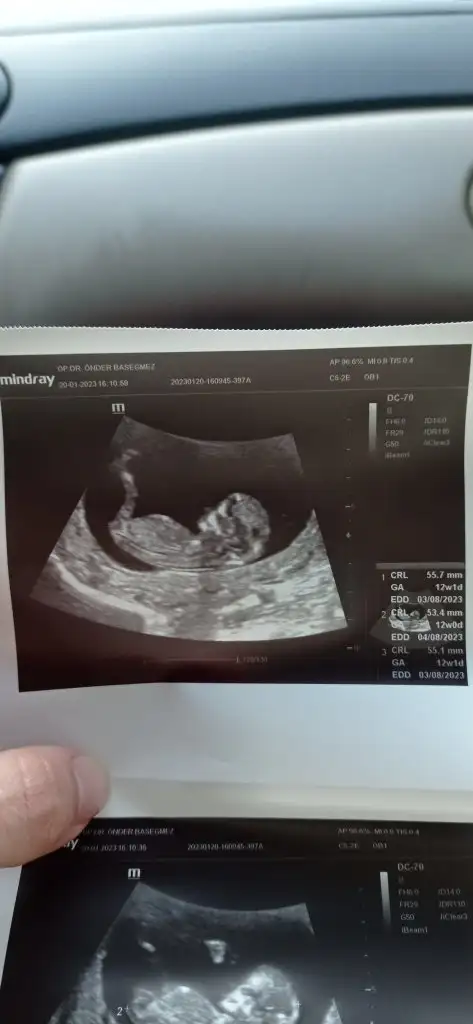

Bize de yorum yapar mısın teyzesi :) Karından ultrason